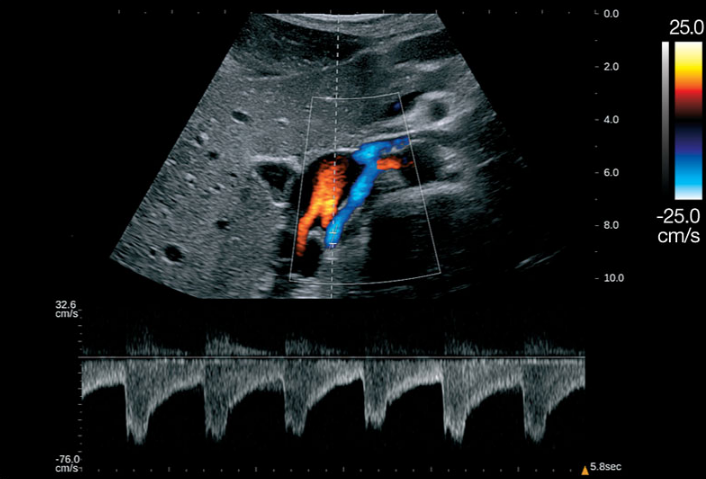

Có 4 kiểu siêu âm Doppler: Siêu âm doppler liên tục, siêu âm Doppler năng lượng, siêu âm Doppler xung và siêu âm Doppler màu. Siêu âm Doppler màu là một kỹ thuật chẩn đoán hình ảnh dựa vào nguyên lý của hiệu ứng Doppler nhằm khảo sát bất cứ dòng chảy nào bên trong cơ thể người. Khi một chùm tia siêu âm được phát đi gặp một vật sẽ phản hồi âm, nếu khoảng cách tương đối giữa nguồn phát và vật thay đổi, tần số của chùm siêu âm phản hồi sẽ thay đổi so với tần số của chùm siêu âm phát đi.

Trong quá trình siêu âm Doppler, bác sĩ đặt đầu dò lên da của người được siêu âm và di chuyển trên vị trí cần kiểm tra. Các sóng âm từ đầu dò phát ra dội lại các vật thể chuyển động và phản xạ tạo ra hình ảnh bên trong cơ thể người. Máy siêu âm sẽ tổng hợp và hiển thị hình ảnh trên màn hình dưới dạng các dạng sóng phổ khác nhau, các màu sắc hoặc tín hiệu âm thanh có thể nghe được.

Bệnh nhân nằm ngửa và thả lỏng toàn bộ cơ thể. Bác sĩ ngồi hoặc đứng phía bên phải bệnh nhân và dùng một loại đầu dò đặc biệt tiến hành siêu âm. Để khám động mạch cảnh trong và ngoài, đầu dò thường bắt đầu khảo sát từ cổ tới góc hàm. Qua kết qua siêu âm Doppler màu, bác sĩ có thể đánh giá thêm tình trạng xơ vữa động mạch nếu có.